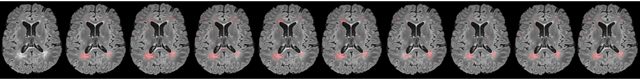

Abstract:To date, several automated strategies for identification/segmentation of Multiple Sclerosis (MS) lesions by Magnetic Resonance Imaging (MRI) have been presented which are either outperformed by human experts or, at least, whose results are well distinguishable from humans. This is due to the ambiguity originated by MRI instabilities, peculiar MS Heterogeneity and MRI unspecific nature with respect to MS. Physicians partially treat the uncertainty generated by ambiguity relying on personal radiological/clinical/anatomical background and experience. We present an automated framework for MS lesions identification/segmentation based on three pivotal concepts to better emulate human reasoning: the modeling of uncertainty; the proposal of two, separately trained, CNN, one optimized with respect to lesions themselves and the other to the environment surrounding lesions, respectively repeated for axial, coronal and sagittal directions; the ensemble of the CNN output. The proposed framework is trained, validated and tested on the 2016 MSSEG benchmark public data set from a single imaging modality, FLuid-Attenuated Inversion Recovery (FLAIR). The comparison, performed on the segmented lesions by means of most of the metrics normally used with respect to the ground-truth and the 7 human raters in MSSEG, prove that there is no significant difference between the proposed framework and the other raters. Results are also shown for the uncertainty, though a comparison with the other raters is impossible.